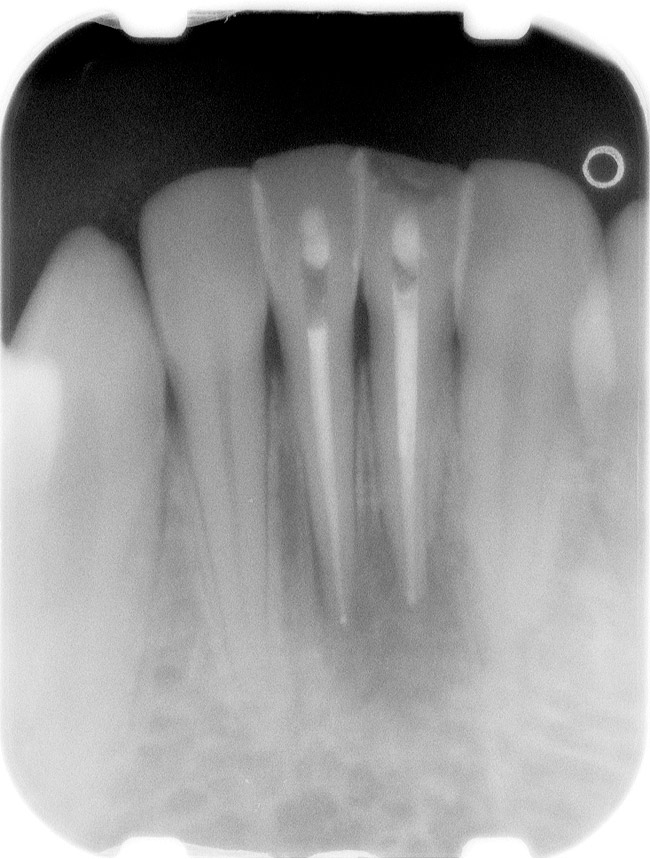

Figure 1  X-ray of an endodontically treated second bicuspid restored with a fiber post, core, and all-porcelain crown.

Figure 1

Case 1

A Class IN maxillary bicuspid was previously restored with a fiber post and an all-porcelain crown (Figure 1). The forces of the oral environment resulted in fracture of the fiber post and crown failure. The remaining fiber post in the root was removed, and anti-rotational areas were prepared for a cast post (Figure 2). A gold cast post was constructed at a dental laboratory, using an indirect technique (Figure 3). A porcelain-fused-to-metal (PFM) crown was constructed with a bevel finish to provide a ferrule and reduce forces on the post (Figure 4 and Figure 5).